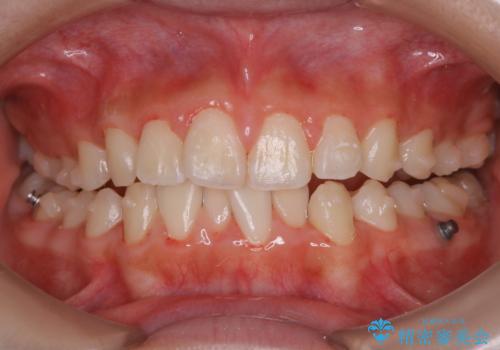

- インビザラインにて矯正治療中の方です。矯正治療の経過チェック時に歯磨き指導とクリーニングも希望とのことでした。

また、矯正で歯の移動があると今までなかったところに隙間が出てきたり、ガタつきが解消されてきたりすることで、お口の中の環境が変わります。